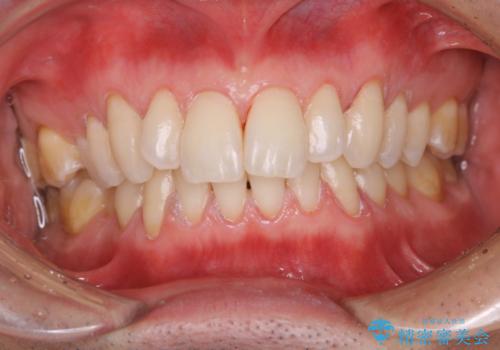

- かなり久しぶりの来院とのことで、クリーニング希望でした。全体的に汚れの付着があったため、PMTCの60分コースを行いました。

PMTCとは、プロフェッショナル・メカニカル・トゥース・クリーニングという、専門家による機械的な歯のクリーニングです。 PMTCは、歯磨きだけでは落とすことのできない細菌・バイオフィルムを除去することが目的です。

歯の健康を守るためには、1回だけで終わらすことなく、定期的にPMTCを行うことがとても大切です。